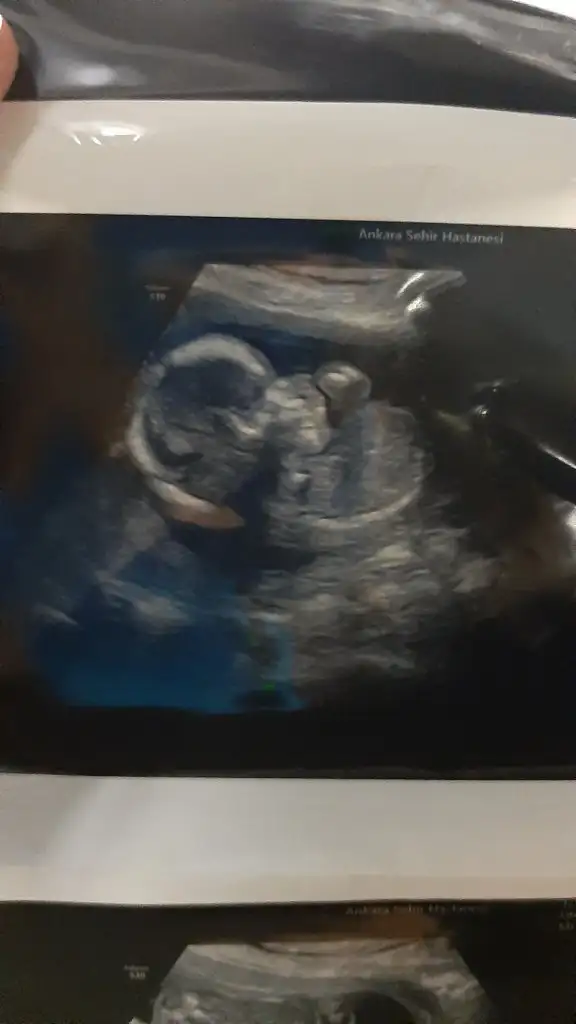

Ayrıntılıyı yaptırdık bugün .. Şükür herşey yolunda Doktor asistana tek tek saydıkça normal dedikçe şükür ettim gözlerim doldu.. 368 gr olmuş 24 cm dedi gayet güzel gelişimi ...Renkli foto da aldık ablası görsün diye.. Sürekli hareket halinde olduğundan en netlerini vermeye çalıştı..Down sendromu riskini %1 bile görmüyorum ama doktorunuzla genetik testini yine de konuşursunuz dedi. Bana kalırsa gerek yok dedi..